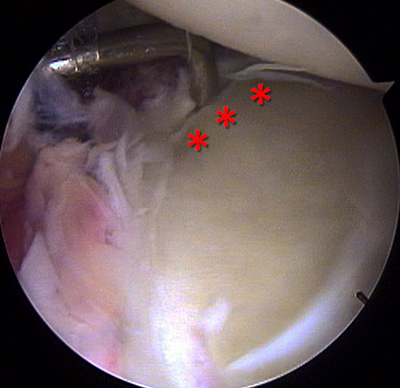

Manteniendo el mismo decúbito lateral, se procedió a realizar un abordaje anterior del hombro, medial a la corredera bicipital y en co-lineación con los portales anteriores artroscópicos, de características reducidas. Se identificó y reparó el tendón del subescapular, él cual fue desinsertado a través de las fibras de sharpey, solo en la porción superior juntamente con la cápsula articular, haciendo un “splinting” de la porción inferior del mismo. Mediante rotación externa se identificó y removió de la articulación el Fragmento Osteocondral libre [F.L.O], observando una delgada capa de hueso sub-condral laminar en la región profunda de la superficie cartilaginosa y con un aspecto macroscópico de buena vitalidad (Fig. 7). La región anterior de la cabeza humeral coincidente con la zona del defecto, fue cruentada hasta lecho sangrante, removiendo el tejido fibroso. Debido a la fina capa del hueso subcondral y al tamaño del F.O.L., se utilizó como sistema de fijación y estabilización dos anclajes óseos de 3.5mm con doble sutura (Fastak®, Arthrex®, Naples, Florida, USA), para lo cual se realizaron 4 perforaciones en el fragmento osteocondral con un Abocath 14 (Fig. 8) y con una técnica pull-in, similar a una sutura en puente, se la redujo consiguiendo buena estabilidad. Esta técnica de sutura consigue tanto una fijación estable como compresión del fragmento de fractura (Fig. 9).

Figura 9: Colocación de dos anclas metálicas de 2,8 mm (Fastak®, Arthrex®), al lecho, realización de una sutura en puente, previa reducción mediante “pull in”.